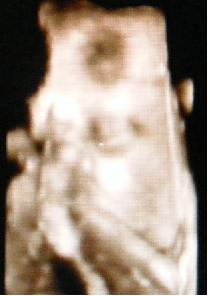

Minden rendben lurkóval, valóban fejvégű, 2100 gr. Kissé nagyobb lesz, mint Bátyja. Megint szóba jött a doki-dolog, hát eléggé meglepődött, amikor mondtam, hogy valószínűleg a dokim nézte el a gyerek fekvését (26. héten faros volt, utána éreztem egy fordulást -egyértelműen-, 30. héten mégis farosnak mondta a doki, azaóta nem éreztem fordulást és most viszont fejvégű (meg ugye előző héten is az volt) ergo szerintem a doki nézte el. No a lényeg, hogy megint beszéltünk erről, de mondtam Neki, hogy már nem akarok nagyon ugrálni... Amúgy a szülésznőmnek mondta, hogy majd együtt szülnek és hogy én leszek az... jééé emlékszik... És lenne mégegy téma ezzel kapcsolatban, de azt nem merem itt nyíltan...